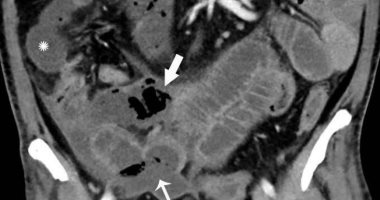

أظهرت النتائج المنشورة في مجلة Radiology علامات تشوهات الأمعاء ومشاكل تدفق الصفراء التى كانت شائعة في فحوصات المرضى، حيث أظهرت حوالي 31 % من الأشعة المقطعية أن المرضى يعانون من مشاكل في جدار الأمعاء.

كما وجد أن المرضى يعانون من حالات بما في ذلك جدار الأمعاء السميك ، وكذلك تكيسات الغاز في جدار الأمعاء والوريد الذي يصرف الدم من الجهاز الهضمي والطحال إلى الكبد.

وكان أحد المرضى لديه ثقب بالأمعاء مثقبة، كما وجد أنه في % من مرضى وحدة العناية المركزة ، كانت هناك علامات على نقص إمدادات الدم إلى الأمعاء.

علق المؤلف المشارك في الدراسة الدكتور راجيش بايانا ، زميل التصوير البطني في قسم الأشعة في مستشفى ماساتشوستس العام في بوسطن ، في بيان نشرته مجلة ” Newsweek” الأمريكية : “لقد وجدنا تشوهات في الأمعاء في التصوير في المرضى الذين يعانون من COVID-19 ، أكثر شيوعًا في المرضى الذين ذهبوا إلى وحدة العناية المركزة.

“كانت بعض النتائج نموذجية لنقص الدم فى القولون أو الأمعاء ، ورأينا جلطات أوعية صغيرة بجانب مناطق من الأمعاء .

وأوضح بايانا: “يمكن أن يعاني المرضى في وحدة العناية المركزة من نقص تروية في الأمعاء لأسباب أخرى ، لكننا نعلم أن COVID-19 يمكن أن يؤدي إلى التخثر وإصابة الأوعية الصغيرة ، لذلك قد يتأثر الأمعاء أيضًا بهذا”.